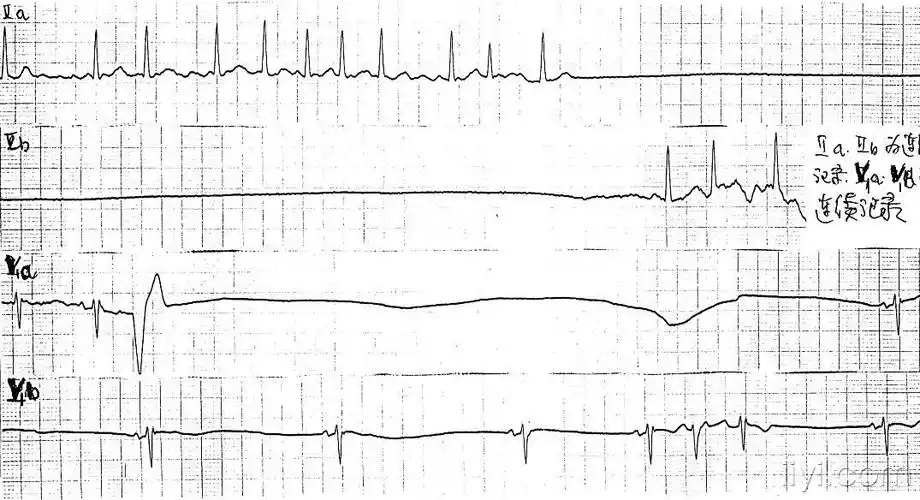

心电机械分离的心监照片分享一下!

将心脏停搏分为三型:(1)心室颤动(心脏不能搏血);(2)电-机械分离(心肌

求:心电机械分离 和心室静止 的心电图图形

求心电机械分离和心室静止的心电图图形